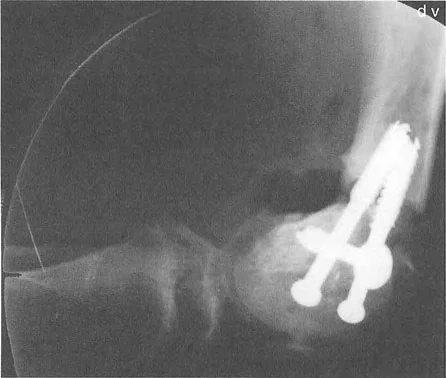

التأثير الجراحي: بسبب هذا التسامح الهندسي، يمكن غالباً إعادة محاذاة سوء المحاذاة الناتج عن إزاحة لقمة الفخذ الأحادية أو سوء توجيهها باستخدام قطع عظم الفخذ فوق اللقمي خارج المفصل. لا تحتاج دائماً إلى تقسيم اللقم وإجراء عملية داخل المفصل عالية المخاطر. على النقيض من ذلك، فإن عدم الاستقرار الشديد الناتج عن درجات عظم الساق يتطلب دائماً تقريباً قطع عظم حقيقي داخل المفصل (رفع الهضبة) بدلاً من مجرد تصحيح في الميتافيزيس، لمنع التدمير السريع للمفصل.

إعادة المحاذاة داخل المفصل رفع الهضبة

إذا قرر الجراح أن هندسة مفصل الركبة غير مقبولة - بسبب عدم استقرار سريري شديد، أو خلع متكرر، أو درجة كبيرة ستدمر الغضروف الهلالي والغضروف المفصلي حتماً - فيجب تحويل التخطيط والتنفيذ إلى تصحيح حقيقي داخل المفصل.

تسلسل التخطيط لرفع الهضبة

تتطلب جراحات قطع العظم داخل المفصل مهارة فنية عالية وتخطيطاً قبل الجراحة لا تشوبه شائبة.